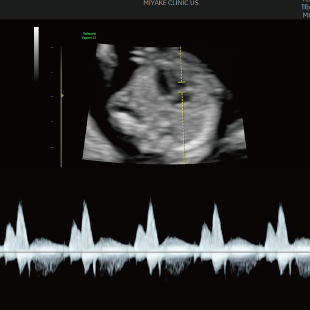

初期スクリーニングでは、首の後ろのむくみ(Nuchal translucency: NT)や鼻の骨、心臓まわりの血流などを確認し、胎児の体の特徴や発育の様子を丁寧に観察します。 これらの所見は、染色体数の変化と関連することがある特徴として知られており、21トリソミー/18トリソミー/13トリソミーなどの染色体変化の可能性を評価する指標となります。(本検査のみで確定診断はできません) また観察可能な範囲において脳や脊椎、心臓、消化管、手足などに大きな形態の変化がないかについても確認を行います。

胎児ドックの様子_初期 胎児ドックの様子_初期 胎児ドックの様子_初期 胎児ドックの様子_初期 胎児ドックの様子_初期 胎児ドックの様子_初期 胎児ドックの様子_初期 胎児ドックの様子_初期